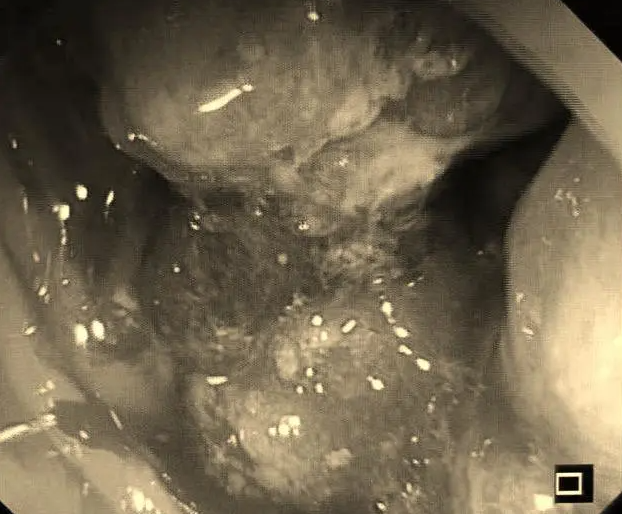

最重要的是,术后问题并没有解决,反而变得更加棘手,没多长时间就出现了持续的便血、体重减轻和全身乏力的症状。又在半年多的治疗后,患者依然没有好转。最终,他听从医生和家人建议,接受了肠镜检查。结果,令人揪心的发现是直肠癌,而且已经是晚期。

巨大占位性病变